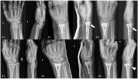

Distal radius fractures (DRFs) are the most common among all kinds of fractures with an increase in incidence due to the rapidly expanded size of the elderly population in the past decades. Both non-surgical and surgical treatments can be applied for this common injury. Nowadays, more and more elderly patients with DRFs undergo surgical treatments to restore pre-injury activity levels faster. However, optimal treatment for geriatric DRFs is still debated, and careful evaluation and selection of patients are warranted considering clinical and functional outcomes, and complications following surgical treatments. Furthermore, osteoporosis is a predominant factor in elderly DRFs mostly deriving from a low-energy trauma, so many treatment modalities are developed to enhance better bone healing. Among various options for bone augmentation, bone cement is one of the most widely used measures. Bone cement such as calcium phosphate theoretically improves fracture stability and healing, but whether the elderly patients with DRFs can significantly benefit from surgical fixation with bone cement augmentation (BCA) remains controversial. Hence, in the present review, the latest literature regarding current concepts of management and evidence about volar locking plate fixation (VLPF) with BCA for elderly DRFs was searched in MEDLINE, Embase, Cochrane Central Register of Controlled Trials, and Web of Science; out of >1000 articles, full texts of 48 and 6 articles were then examined and analyzed separately for management and VLPF with BCA for elderly DRFs. We aim to provide the readers with updates concerning the above issues.